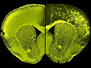

The dentate gyrus is a part of the brain that contributes to the formation of memories. In individuals with Alzheimer’s disease, this is the first site known to undergo degenerative changes even before symptoms start to show. This sounds promising for detecting Alzheimer’s earlier, but this structure is only a few millimetres thick and hidden deep within the brain. To exploit this knowledge, we would need really powerful imaging techniques to detect microscopic changes. Here, researchers used a 16.4 Tesla MRI scanner – a much stronger magnetic field than currently used for human body imaging – to measure changes for example in neuron density and abnormal protein accumulation within the dentate gyrus from postmortem brains of cognitively normal individuals (left) and those with Alzheimer’s (right). Colours highlight neuron fibres in subregions, revealing differences. While this technology is far from ready for a clinical setting, it is a step in the right direction.